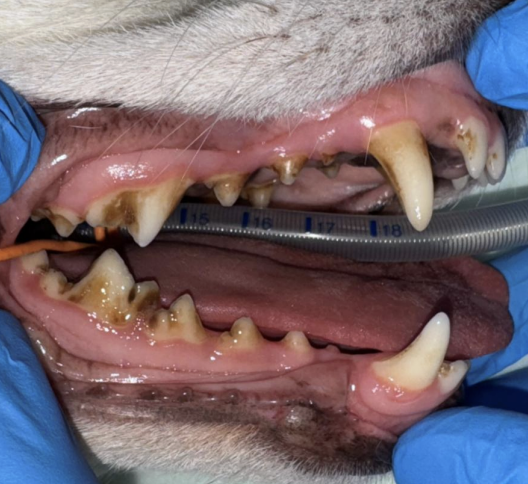

・Before

歯石の沈着と口臭を気にされていました。

歯磨きも挑戦されているようですが、うまく磨けず歯石がついている状態でした。

特に奥歯に歯石がついており、一部赤みや腫れている部分も認められました。

専門の器具を使い、歯の表面や歯周ポケットの歯石をきれいに取り除く処置「スケーリング」を行いました。

その後、歯の表面をなめらかに磨いて仕上げました。これは歯の表面の細かい傷をなめらかにすることで、歯石が付きやすくなるのを防ぐために行います。